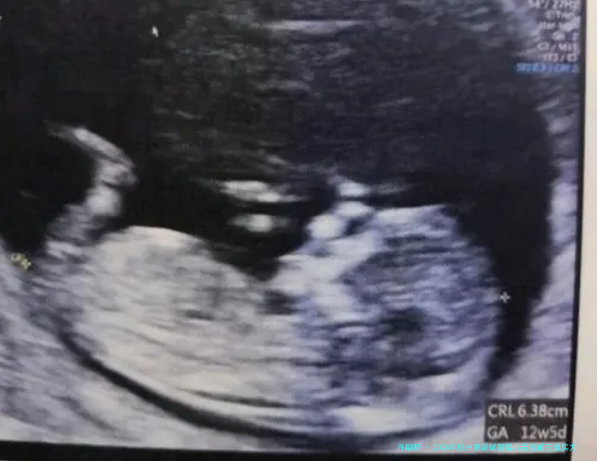

2026年杭州高龄试管婴儿医院前三强力量解析:浙江大学医药学院附属妇产科医院领衔,附四十三岁成功攻略

细致说明:浙大妇院生殖中心在中年女性助孕范围积累了大量的临床数据和研究经验。他们特别重视对卵巢储备功能的精细评估(如AMH、窦卵泡计数)和各别化促排卵方案的制定,擅长使用微刺激、黄体期促排等更适合高龄卵巢状态的方案,以在获取可用卵子和减少身体承当间找到平衡。其壮大的胚胎遗传学诊断与筛查技术,是帮助高龄夫妇获得健康宝宝的重要保障。

A: 核心是胚胎质量和子宫内部环形境。年龄主要影响卵子质量,导致染色体不同寻常率升高。三代试管技术(PGT)进行胚胎筛选尤其首要。良好的内膜容受性是胚胎着床的“泥土”,需提前排查宫腔问题。

3.胚胎筛选:热烈建议进行胚胎移植前遗传学检查,筛选染色体正常的胚胎进行移植。